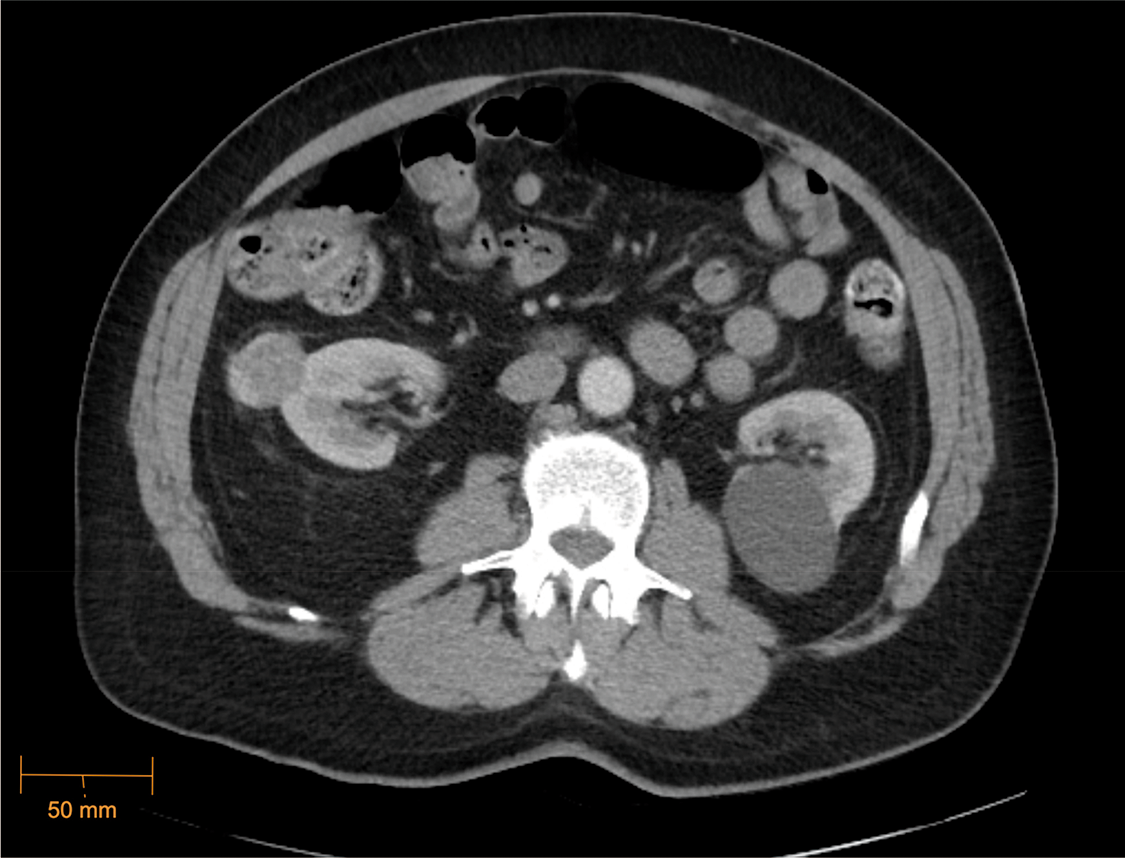

A 69-year-old male presented to the urology clinic with a renal mass incidentally found on CT after presentation to the emergency department with cholecystitis. Cross-sectional imaging identified an enhancing 3.3 × 2.6 cm exophytic mass of the lateral right kidney (Figure 1), and notably, lung adenopathy in the left hilum (Figure 2), initially concerning for metastasis from a renal primary. The patient was referred to interventional radiology and biopsy of the renal mass and hilar lymph nodes. The renal mass biopsy was completed successfully, but the hilar adenopathy was unable to be accessed percutaneously. Review of renal lesion pathology demonstrated a component of oncocytoma with a secondary component of low-grade spindle cell NET.

Figure 1: Enhancing right renal mass, CT Abdomen/Pelvis (axial) (5/21/2023)